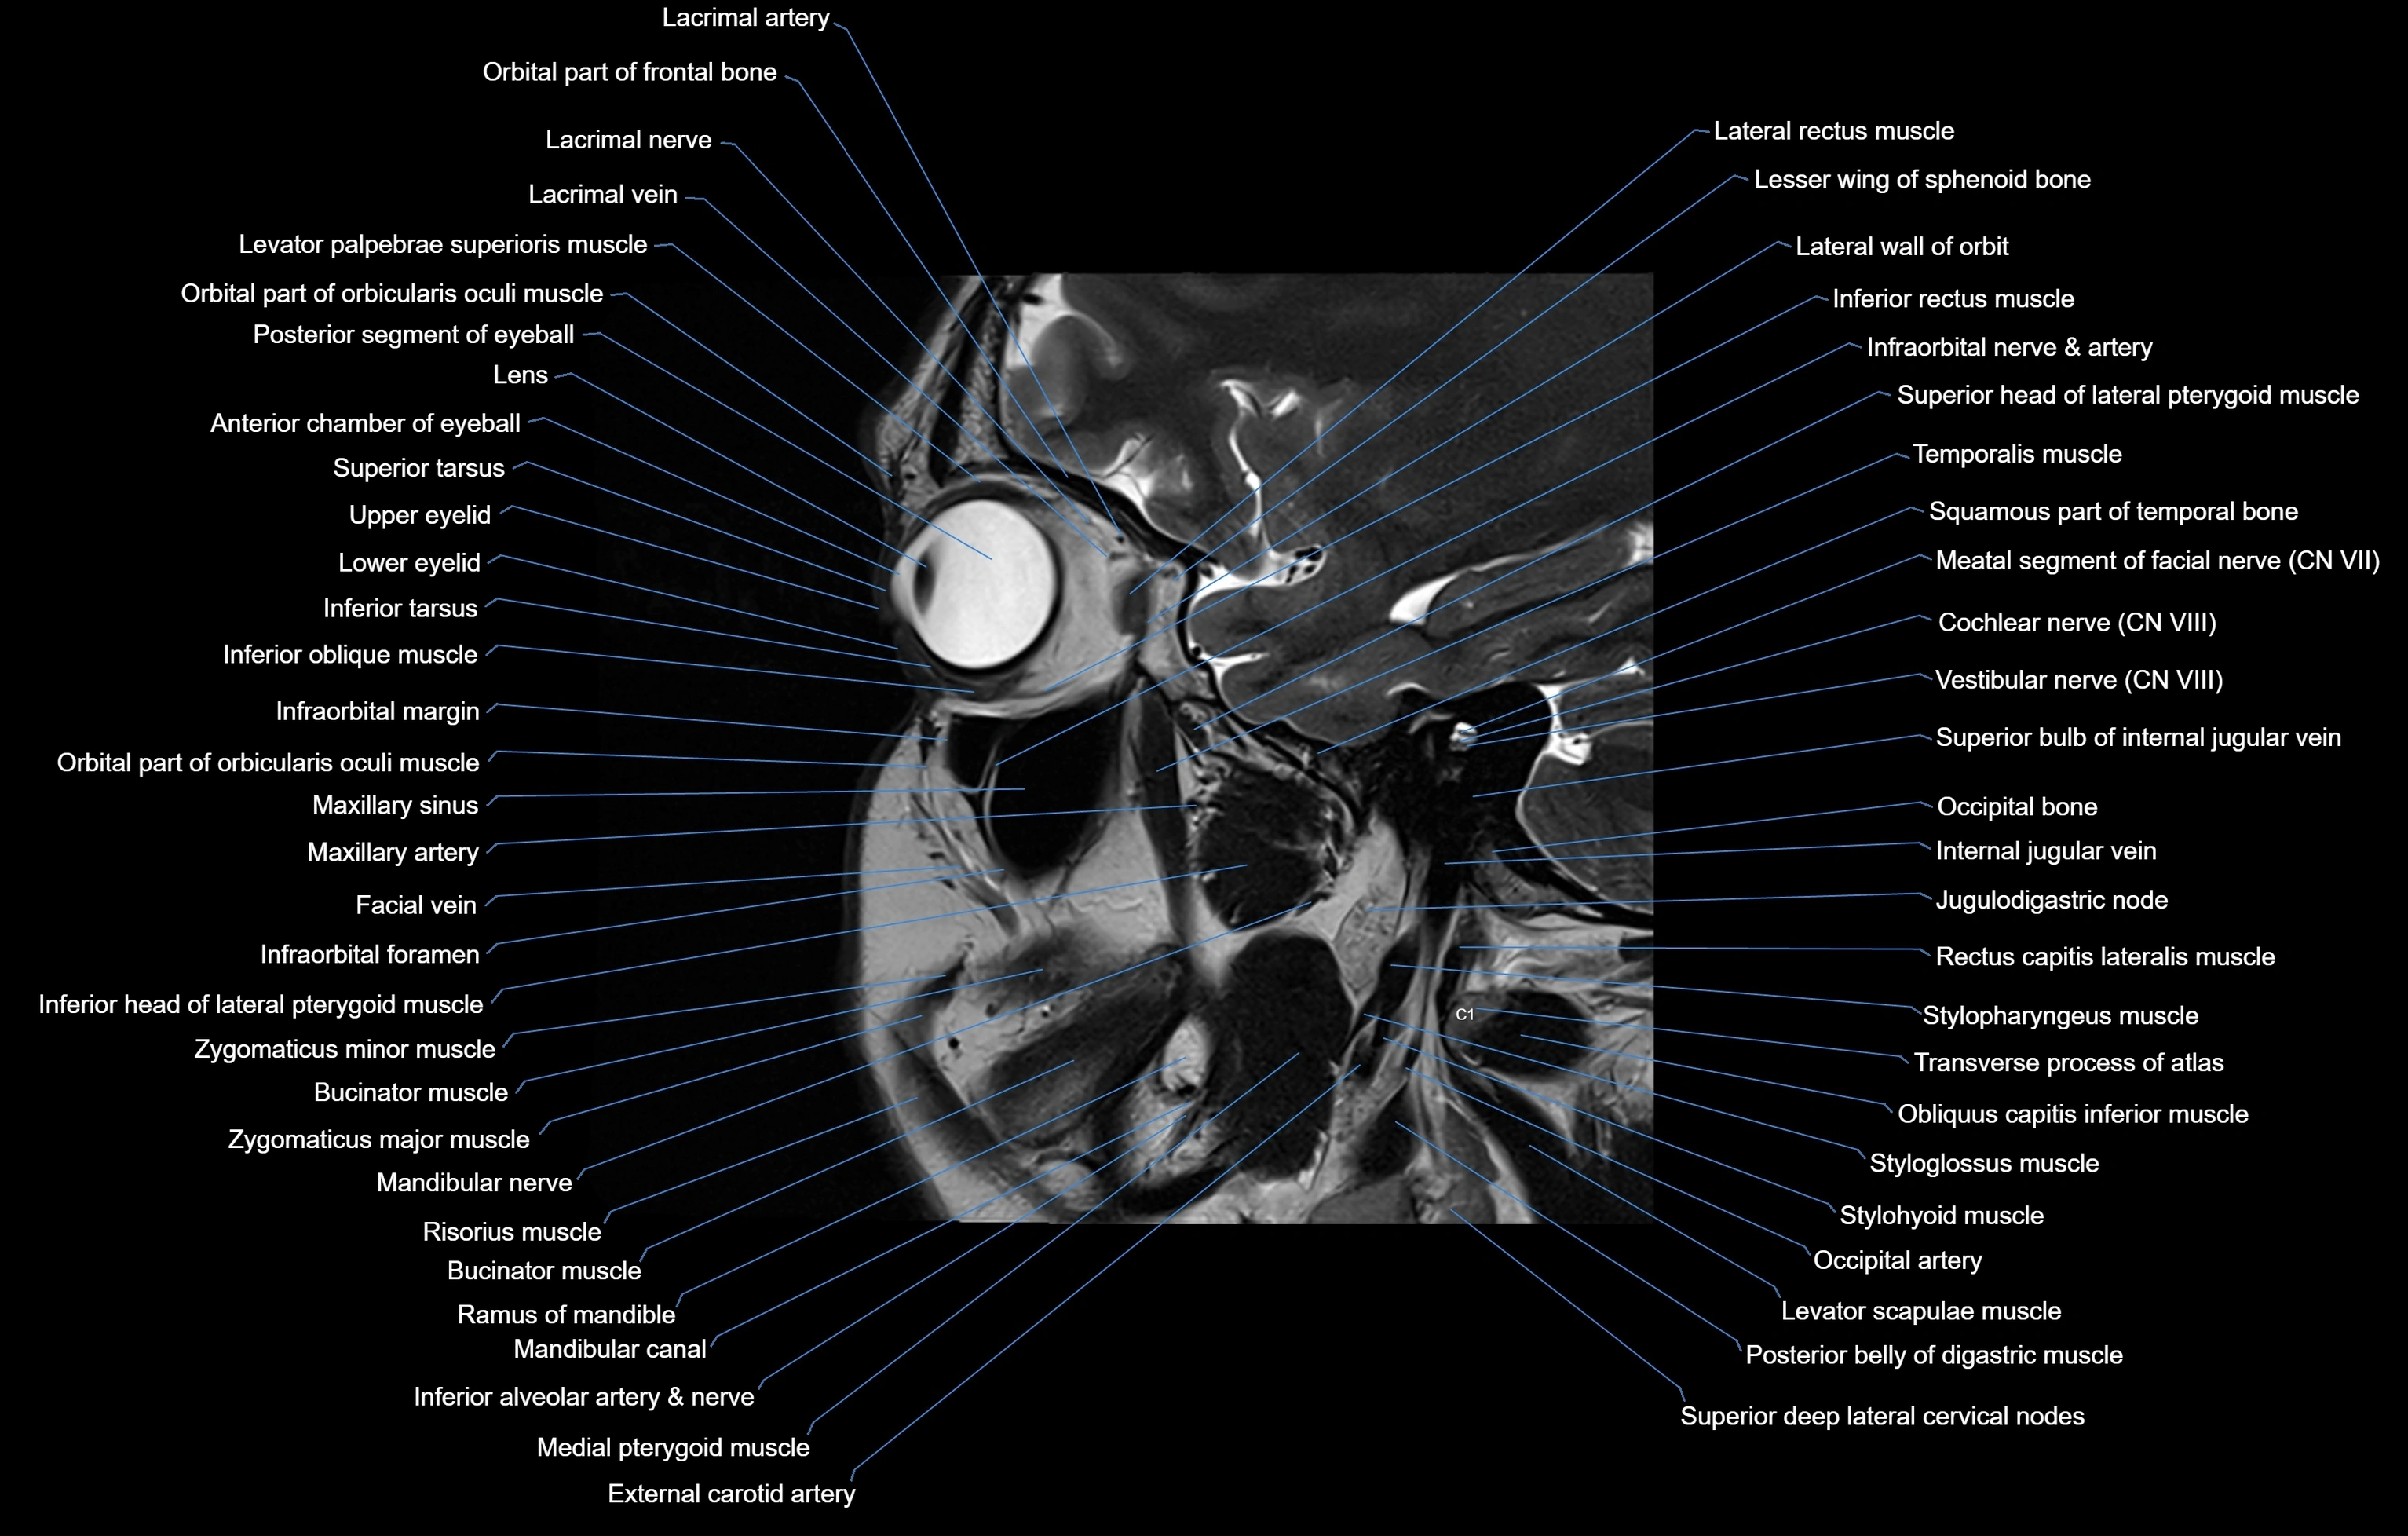

MRI images